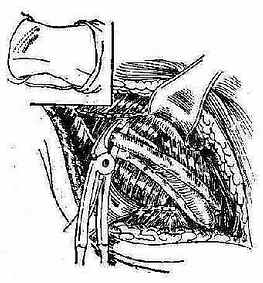

③经侧胸部引流:适用于右肝上间隙的高位膈下脓肿,此途径须经过胸腔肋膈角部分,除非原有胸膜疾病此处已粘连闭合,否则均应分二期进行。第一期在侧胸部第8或第9肋处作切口并切除一小段肋骨直至胸膜。然后用碘仿纱布和酒精纱布填塞伤口,使引起周围粘连一周后再行第二期手术时即可在穿刺定位后,切开已粘连的胸腔肋膈角,直达脓肿置管引流。